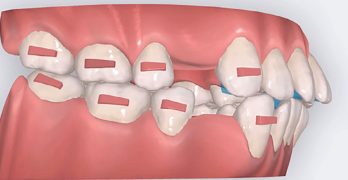

Biomecánica de extracciones de premolares con alineadores: reporte de caso y revisión de literatura

El artículo que compartimos el día de hoy se llama Biomechanically Valid Clear Aligner Therapy for Premolar Extraction … [Leer más...] acerca de Biomecánica de extracciones de premolares con alineadores: reporte de caso y revisión de literatura